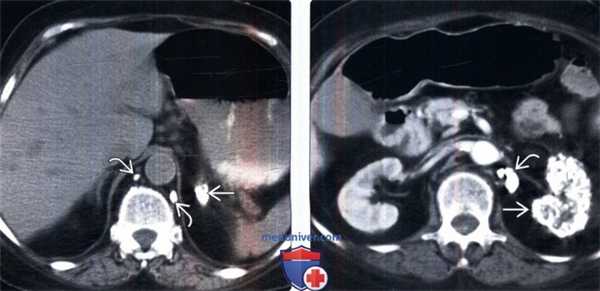

(Слева) Бесконтрастная КТ, аксиальная проекция: очаги кальцификации в забрюшинных лимфатических узлах и левом надпочечнике В (случайные находки у женщины пожилого возраста). Правый надпочечник без изменений. Одностороннюю гранулематозную инфекцию надпочечника встречают редко.

(Справа) КТ с контрастированием, аксиальная проекция: у этой же пациентки выявлена выраженная кальцификация нефункционирующей левой почки В (типичная «цементированная» почка вследствие туберкулеза). Обратите внимание на дополнительные кальцификаты.